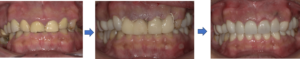

歯冠長延長術とセラミック治療を組み合わせた場合、治療費と期間を短縮する事も可能で

す。以下の症例のように、歯の形と色を自由に選ぶことができます。

この患者さんは奥歯にはインプラントも行い、咬み合わせを上げる治療も行い、しっかり

食事ができるようになったと喜んでもらえました。

その後に、前歯はホワイトニングや歯冠長延長術とセラミック治療を行い審美回復し、自

信をもって笑えるようになったそうです。

(1日目)治療計画をご納得いただいた上で仮歯の歯型をとります。

(2日目)歯肉を切除し、歯を支えている骨を状態に応じて削ります。

その日のうちに前歯を削り、仮歯を装着しガミースマイルを改善します。

(3日目)抜糸時にセラミックの精密印象を行います。

(4日目)歯の長さや色など、ご要望に合わせたセラミックを被せて完了です